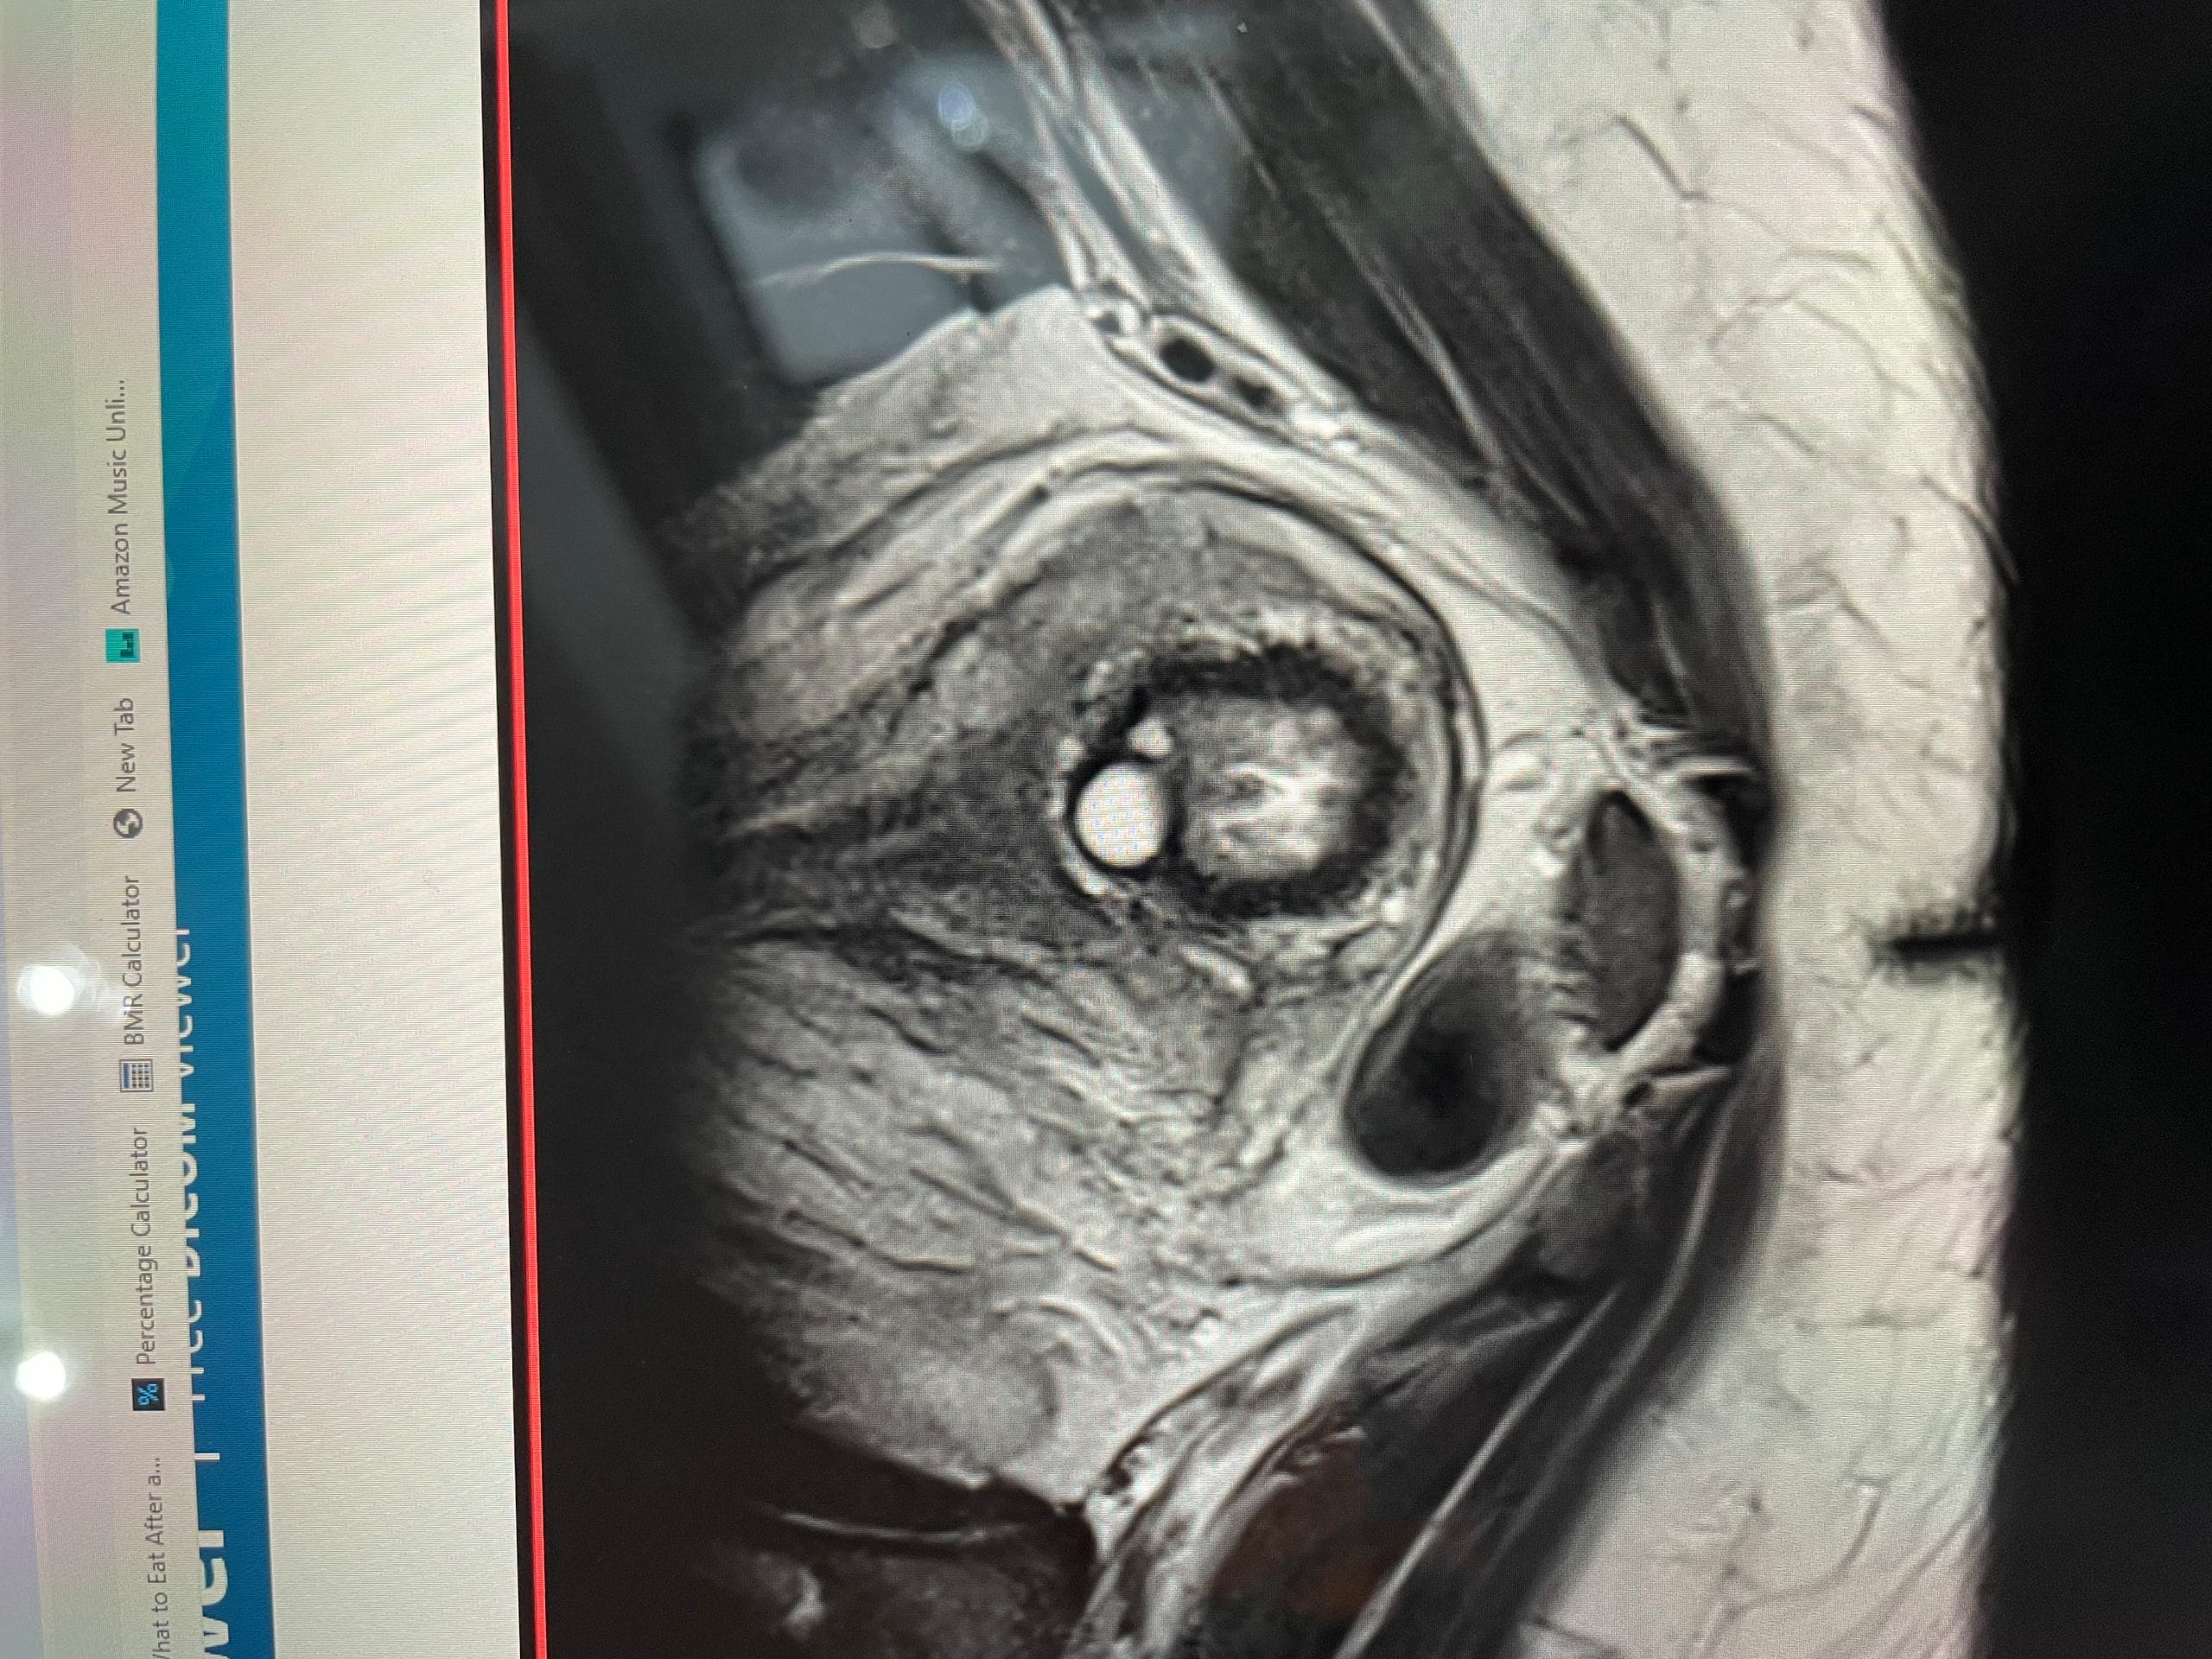

I have been having some

terrible trouble with pain my leg and back and have seen a specialist who sent me for an MRI on my Sacrum/sacroiliac joints - have noticed what I think might be a cyst but I am not sure if it’s either my stomach or uterus - it’s a while until my next appointment and going a bit stir crazy wondering if anyone had any thoughts?